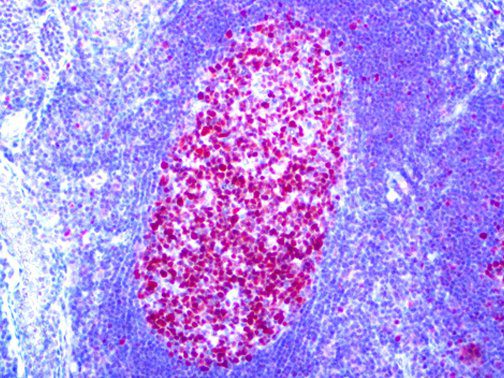

It is the ICU physician who is most likely to witness one of the deadliest manifestations of the abnormal immunological response, the cytokine storm syndrome (CSS). This response is also referred to by some as the cytokine release syndrome (CRS). CSS is characterized by continuous activation and expansion of macrophage and lymphocyte populations, which secrete large amounts of cytokines, causing the cytokine storm. This massive cytokine release is akin to hemophagocytic lymphohistiocytosis (HLH) disease, a syndrome characterized by initial unchecked and persistent activation of cytotoxic T lymphocytes and NK cells.

Clinical and laboratory manifestations of HLH include fever, enlarged liver and/or spleen, neurologic dysfunction, coagulopathy, liver dysfunction, cytopenias (i.e., low levels of erythrocytes, leukocytes, and/or platelets), hypertriglyceridemia, hyperferritinemia, hemophagocytosis, and eventually diminished NK cell activity as the immune system becomes progressively paralyzed. HLH can be familial (primary HLH) or secondary to another disease process (sHLH), such as rheumatic disease, in which it is referred to as macrophage activation syndrome (MAS, characterized by elevated ferritin).